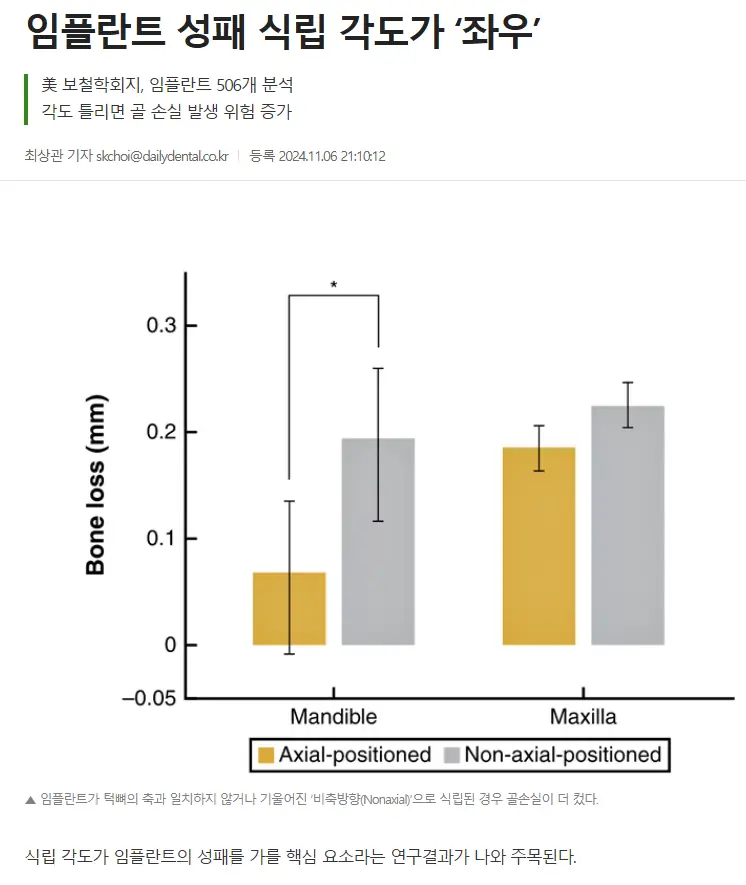

임플란트 치료를 앞두고 계신 분들이 걱정하는 부작용 문제, 사실 올바른 진단과 계획, 맞춤형 수술, 그리고 꾸준한 사후 관리가 가장 중요하다는 점을 알려드리고 싶어요. 임플란트는 단순히 치아를 심는 수술이 아니라, 앞으로의 생활과 건강까지 고려하는 치료이기 때문에, 뼈와 잇몸 상태를 꼼꼼히 살피고, 개인별 맞춤 수술이 필요하죠. 특히 뼈가 부족하거나 잇몸이 약한 분들은 보강이나 특수 임플란트가 도움이 될 수 있어요. 수술 후에는 정기검진과 올바른 구강 위생 습관이 필수입니다. 집에서도 치실이나 양치법을 잘 지키고, 정기 검진을 통해 잇몸과 뼈 상태를 체크하는 것이 부작용 방지와 오래 쓰는 비결입니다. 임플란트는 완성품이 아니라 관리품이라는 마음가짐으로 꾸준히 관리하는 것이 중요하니, 치료 전후의 철저한 준비와 관리로 건강한 치아를 오래 유지하시길 바랍니다.